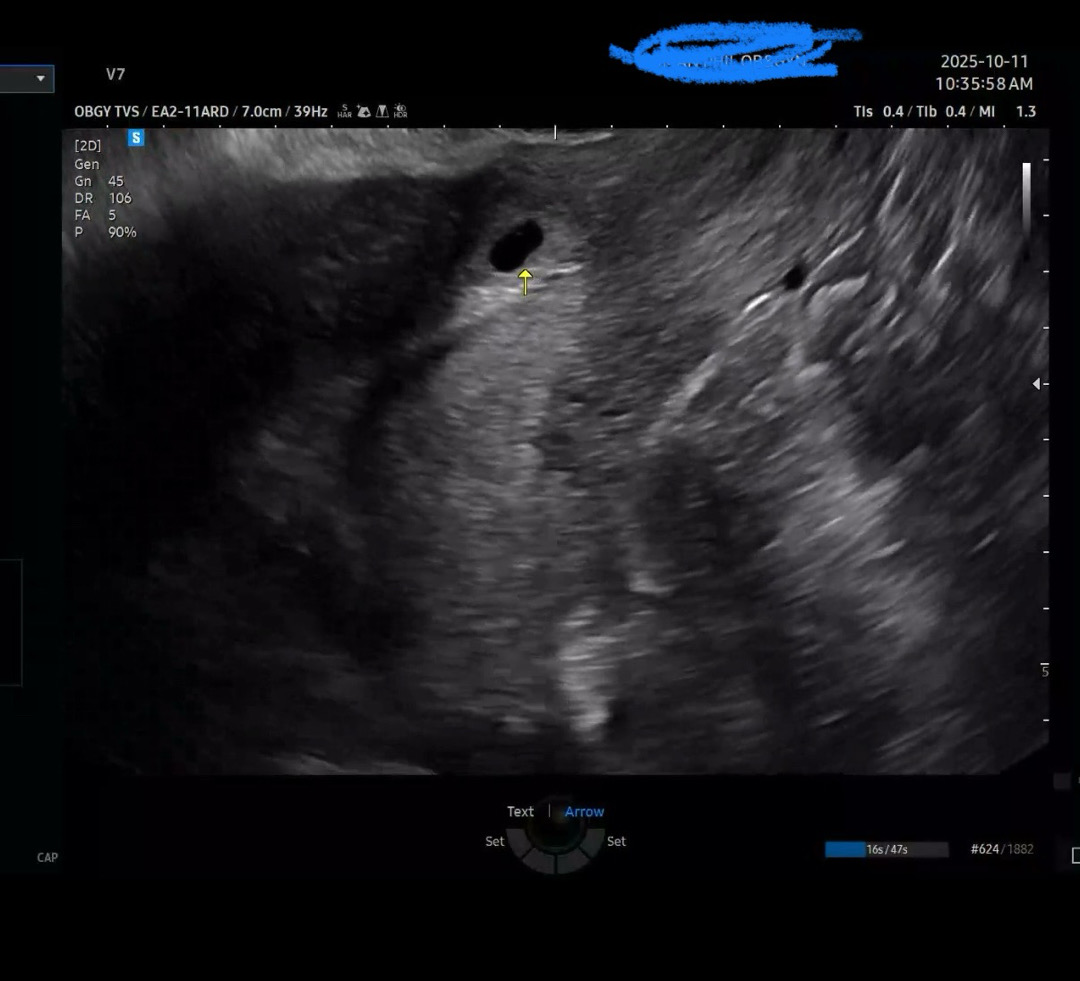

막생 9/7일 아기집보러갓는데.. 제왕절개 한곳 근처에 아기집이 생겼다네요ㅠ 작년이맘때쯤.. 둘째 떠나보내고 다시 온 둘째인데.. 밑에쪽에 자리 잡앗다니 걱정이 엄청나네요ㅠ 병원가려면 2주나 남았는데! 아기집이 위로 올라갈 가능성이 있을까요ㅠㅠ 너무정신 없어서 물어보지 못하고왓거둔요ㅠㅠ